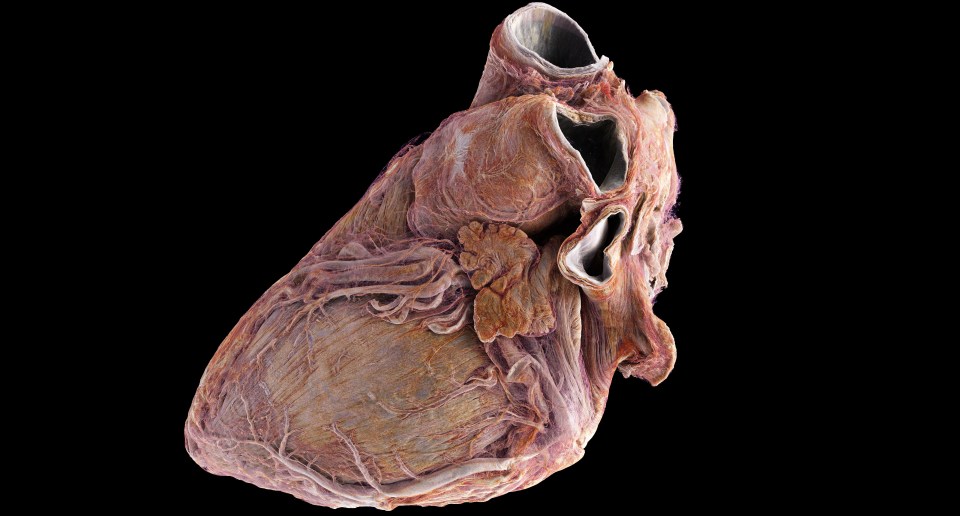

Lekári zvyčajne používajú zobrazovacie techniky, ako je ultrazvuk, CT a MRI, na diagnostiku kardiovaskulárnych ochorení, ale tie neposkytujú podrobné štrukturálne informácie o tom, čo sa deje v orgáne. Teraz vedci vytvorili prvý atlas ľudského srdca na svete, ktorý pripomína Google Earth a ponúka bezprecedentný pohľad do zdravého a chorého srdca. Technológia poskytuje podrobné snímky až do hĺbky 20 mikrometrov, čo umožňuje 3D pohľad na celý orgán so zobrazením na úrovni buniek v určitých oblastiach.

Tento prelomový objav by mohol priniesť revolúciu v chápaní a liečbe kardiovaskulárnych ochorení vrátane arytmie. Pomocou prelomovej röntgenovej techniky nazvanej hierarchická fázová kontrastná tomografia (HiP-CT) vedci z University College London a Európskeho zariadenia pre synchrotrónové žiarenie (European Synchrotron Radiation Facility – ESRF), čo je najjasnejší röntgenový zdroj na svete vo francúzskom Grenobli, neuveriteľne podrobne zobrazili dve celé srdcia dospelých ľudí.

Táto technológia ponúka globálny pohľad na orgán a odhaľuje štruktúry a spojenia, ktoré predtým neboli známe. Cieľom štúdie je zlepšiť možnosti liečby a chirurgického výcviku poskytnutím realistických modelov srdca. Zobrazovanie každého srdca vygenerovalo 10 terabajtov údajov, čo je miliónkrát viac ako pri štandardnom CT vyšetrení.